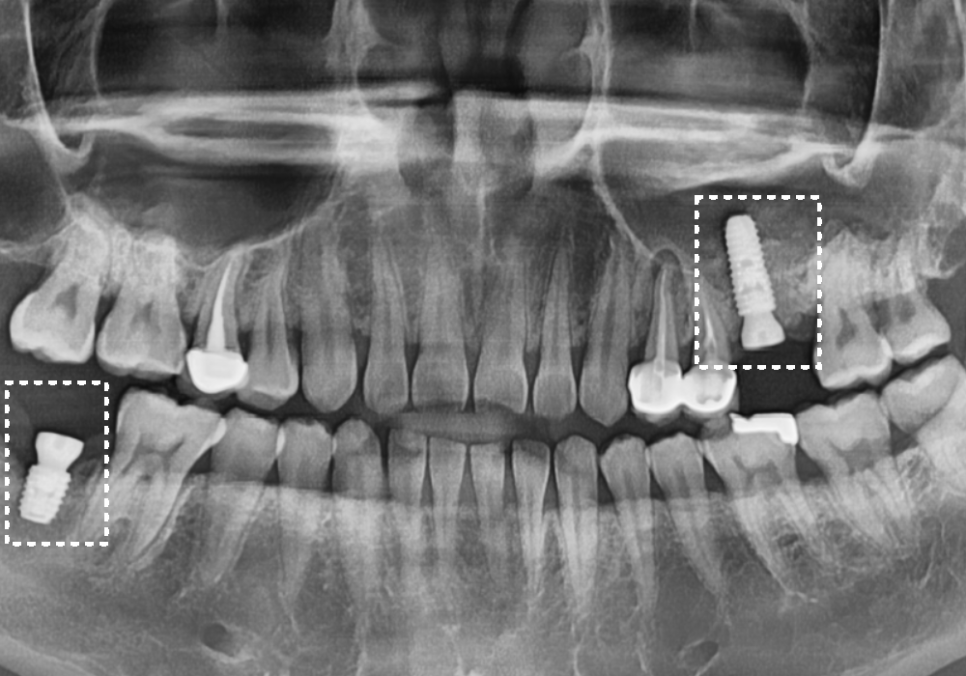

방사선 사진상으로는 상태가 더 심각했는데요.

보이는 것보다 충치가 훨씬 깊게 파고들어,

마치 겉면만 간신히 남고

속은 텅~비어버린 상태였어요.

더 주의 깊게 보아야 할 곳은

겉보기에 큰 충치가 없어 보였던

오른쪽 아래 치아였습니다.

방사선 사진을 보니 치아 주위의 뼈가

상당 부분 소실되어,

치아가 잇몸뼈 위에 불안정하게

떠 있는 상태였거든요.

진단 결과, 위아래 모두 치아를 살리기 어려워

발치 후 임플란트를 진행하기로 했습니다.

하지만 두 곳 모두 임플란트를 심을 뼈가 부족하여

뼈이식이 반드시 필요한 상태였는데요.

아래쪽(#47): 신경관 인접성

오른쪽 아래 역시 CT 상에서 확인하니

뼈가 신경관 바로 근처까지 녹아 있네요.

임플란트를 지탱해 줄 뼈가

거의 없는 상태였기에,

이럴 경우, 뼈이식을 진행하여

임플란트가 안정적으로

식립될 수 있는 환경을 먼저 만들어야 합니다.